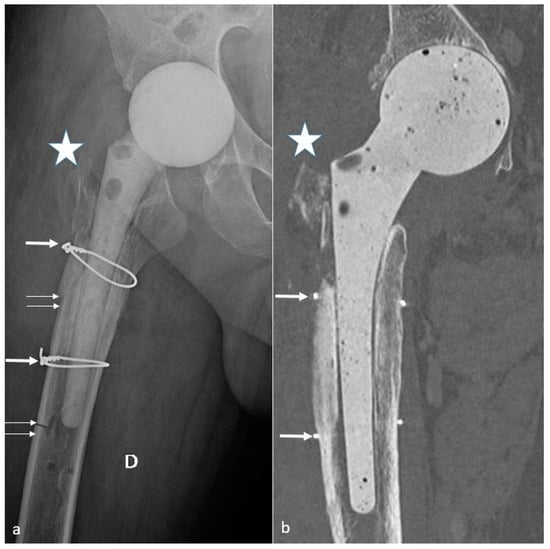

4.10. Peri-Prosthetic Fractures and Stress Reactions

4.10.1. Background

4.10.2. Imaging